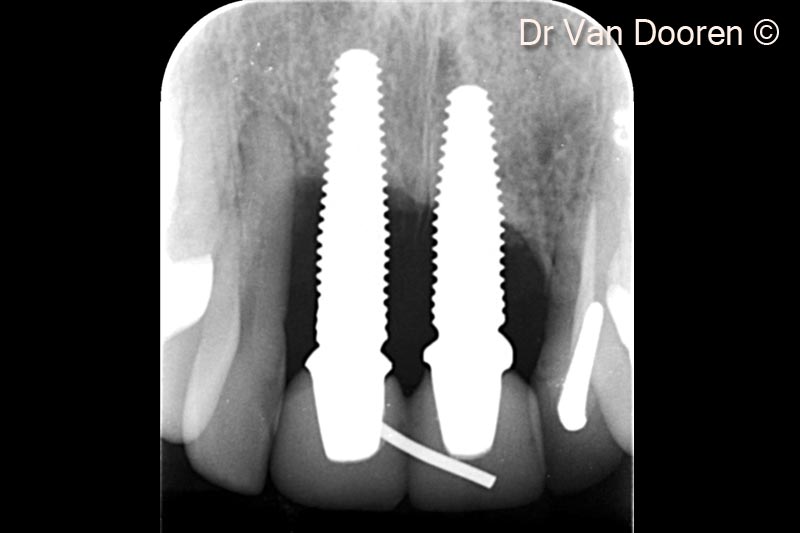

Ảnh chụp X-quang cuối cùng. Lưu ý mức độ xương viền ổn định xung quanh implant và sự tích hợp tốt của vật liệu ghép (OsteoBiol® GTO®) trong khoang quanh implant.